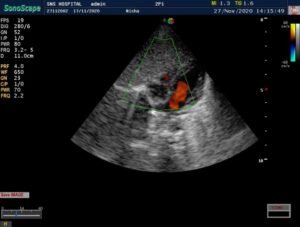

CARDIAC screening of the baby was done – is fourth week of life. Showed –

> Acyanotic congenital heart disease.

VSD – 5mm – muscular non –

restrictive.

ASD – 4mm – L-R shunt

PDA – 2.5mm – L-R shunt. Baby under follow up.